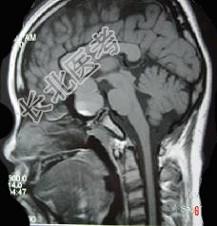

- 单项选择题男,47岁, 视物模糊数月,头痛、恶心、呕吐3天, 行MRI检查如图,最可能的诊断是 ( )

A、垂体瘤并出血

B、表皮样囊肿

C、颅咽管瘤

D、蛛网膜囊肿

E、脑膜瘤